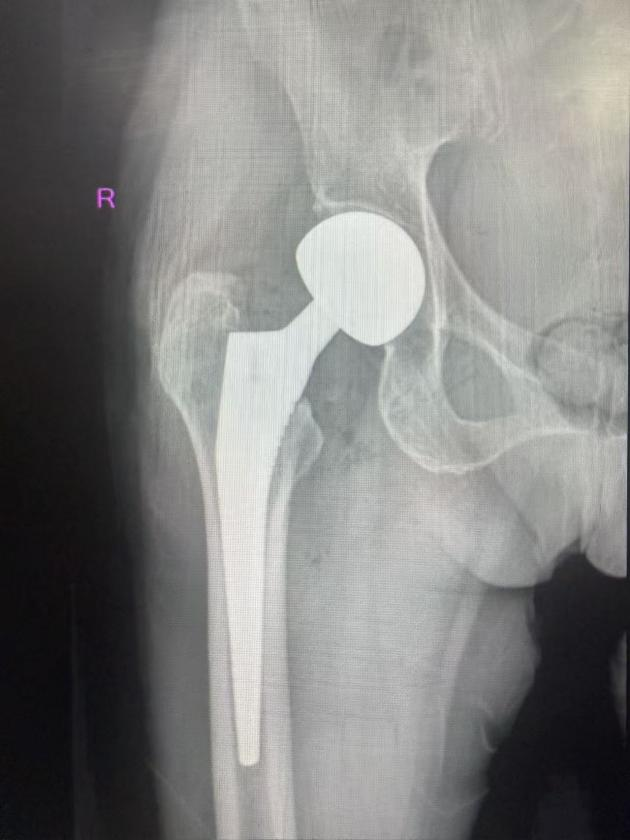

经过充分的术前准备,经验丰富的赵军主任医师主刀,为李奶奶成功实施了“右侧人工双动股骨头置换术”。手术过程顺利,出血量少,历时不到一小时。

术后,李奶奶被送入病房,医护人员立即开始了精心的护理和早期的康复指导。麻醉苏醒后,在康复治疗师和护士的协助下,李奶奶当天就开始进行踝泵练习、股四头肌等长收缩等床上功能锻炼。术后第二天,她便在家属和助行器的辅助下成功下地站立,迈出了康复的第一步。

住院期间,骨科团队根据李奶奶的恢复情况,每日调整康复计划,并密切监测她的生命体征和伤口情况。营养科也为她制定了个性化的营养支持方案,促进伤口愈合和体力恢复。在医护团队的共同努力和家人的悉心陪伴下,李奶奶恢复神速,术后一周已能借助助行器在病房内独立短距离行走,疼痛基本消失,精神状态良好。

出院前,医生为她制定了详细的家庭康复计划和定期复查安排。术后一个月,李奶奶回院复查,关节功能恢复良好,生活基本自理,对手术效果和整个治疗过程表示非常满意。